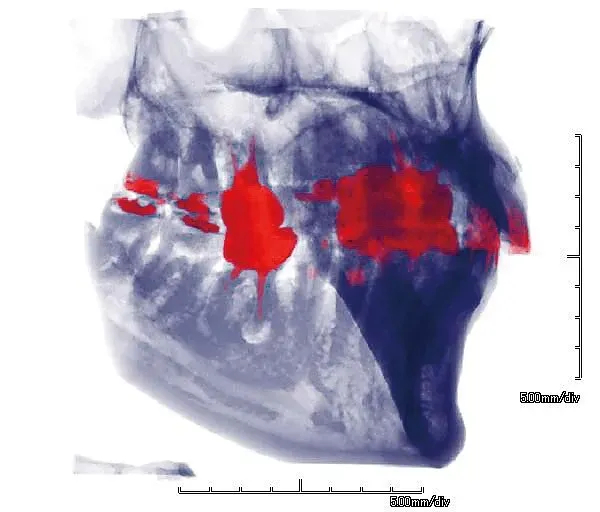

ファインキューブE2【アーム型X線CT診断装置】

ファインキューブのDNA、高画質・操作性の良さを引き継ぎ第2の進化を遂げ、より身近になったファインキューブ。新たにセファロ搭載機種もラインナップ。